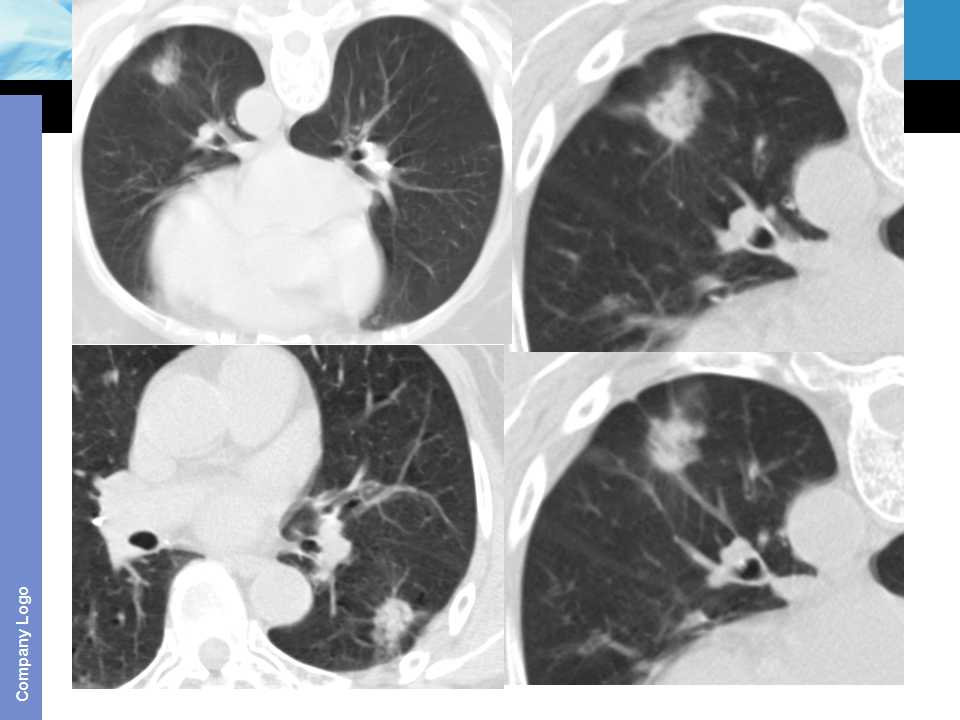

肺癌影像诊断